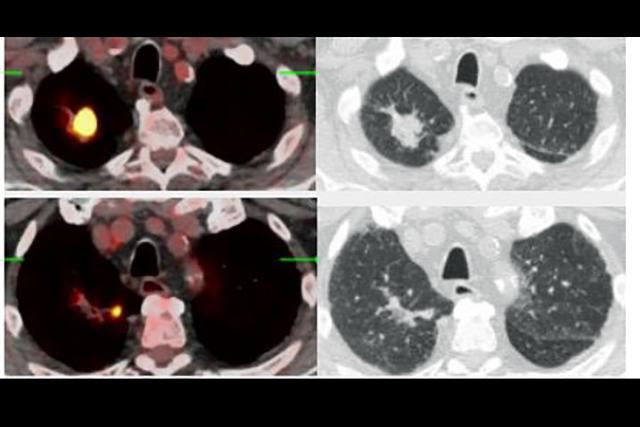

The award to UW Medicine Radiology will support efforts to help patients diagnosed with cancer understand their imaging reports. Dr. Majid Chalian, associate professor of radiology, will lead this work. An AI program will extract and translate radiology report findings to prepare clear, plain-language explanations of the results. A mix of healthcare experts will review these and give feedback to the AI model so it can learn, constantly improve, and reduce misunderstandings. The hope is that this approach, as its accuracy and adaptability is enhanced over time, will foster better communication between medical professionals and their patients.